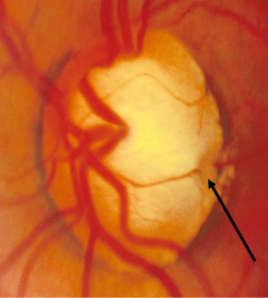

coloboma of ONH

ONH coloboma